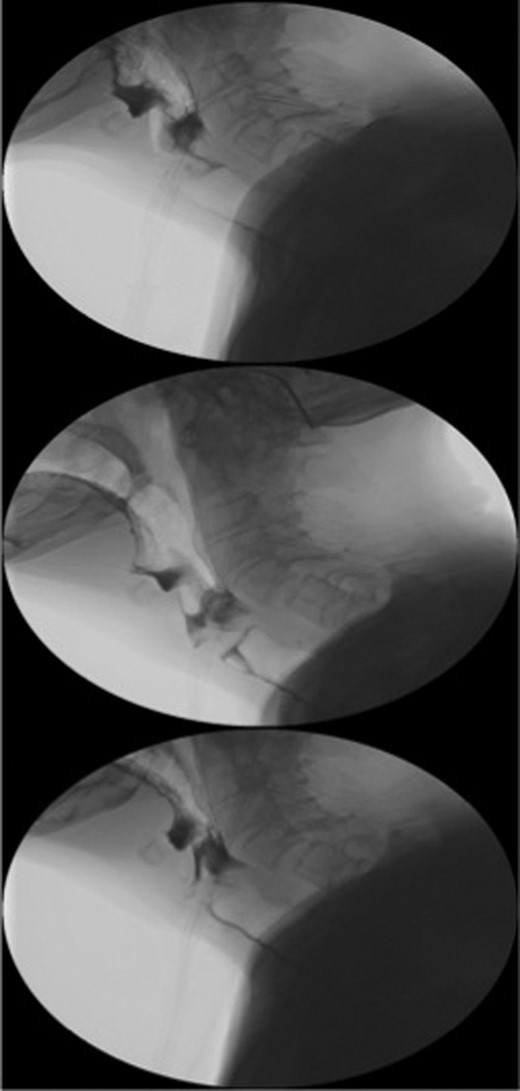

A 95-year-old Caucasian woman presented with worsening dysphagia, epigastric pain, retching without vomiting and hiccups over 5 months. Oesophagogastroduodenoscopy (OGD) was unsuccessful due to failed intubation. Fibreoptic nasoendoscopy revealed pooling of saliva in the piriform fossa and a diagnosis of pharyngeal pouch was initially made. Barium swallow was abandoned due to aspiration by the patient (Fig. 1).

Sequence of barium swallow examinations revealing upper oesophageal tightening and aspiration.